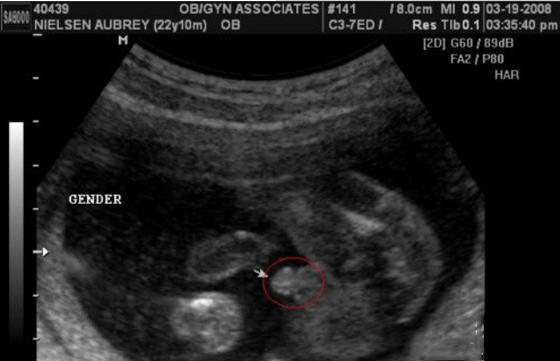

男宝宝B超图:

男宝宝的B超图上其实是能看到小鸡鸡的,图片的红圈处就是。这张图片上的小鸡鸡非常清晰,医生很厉害,她取的那个角度就是宝宝的屁股正下方,看的特清楚。

“凸出的东西” 是他的标记: 你们看到圆圆的是DANDAN,如果看到圆圆的加小肠的就是全部JJ。